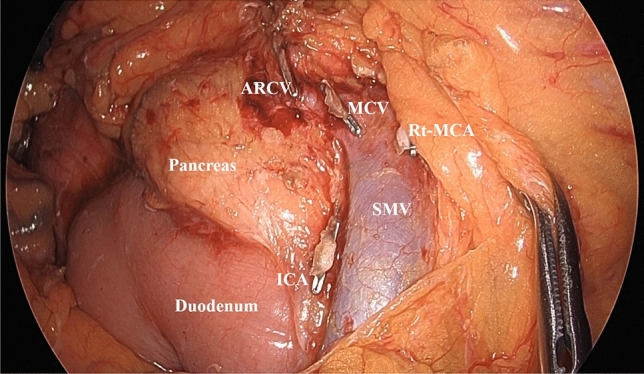

Background: Right-sided colon cancer surgery is a highly difficult operation, and ensuring perioperative safety is an important issue. While various approaches have been proposed for right-sided colon cancer, there are few reports comparing them. The present study compared the inferior approach (IA) and medial approach (MA) for right-sided colon cancer surgery and evaluated their safety.

Methods: We compared 528 cases of right-sided colon cancer surgery performed at our five affiliated institutions from 2017 to 2023, divided into IA and MA groups of 122 cases each using propensity score matching. Short-term outcomes of both groups were retrospectively evaluated, focusing on perioperative complications and perioperative mortality as the primary outcomes.